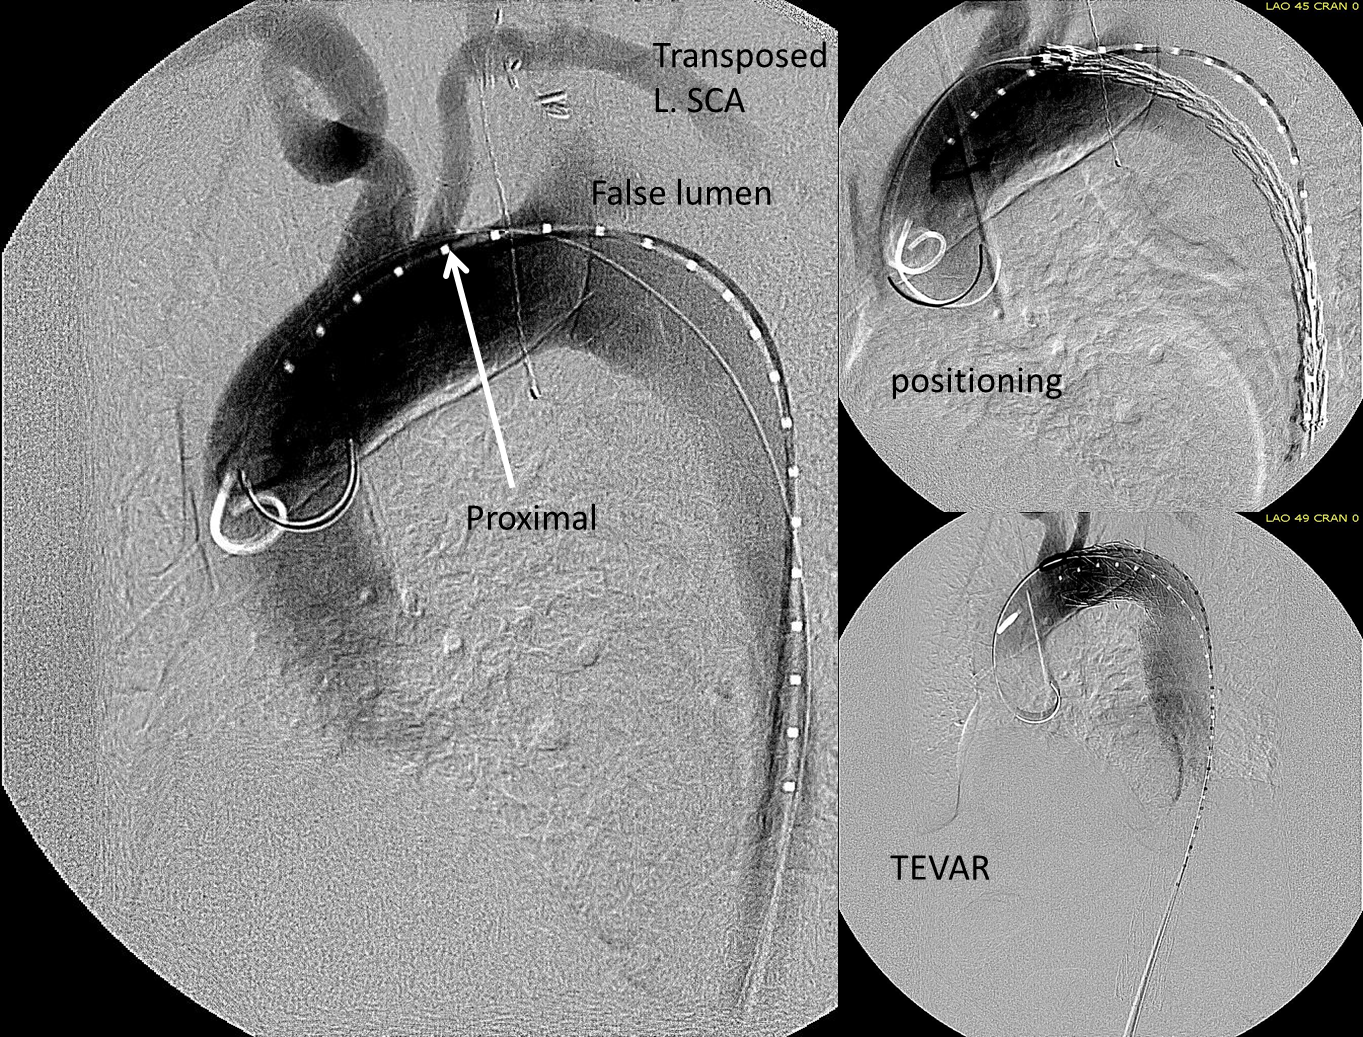

The patient is middle aged and had a type B thoracic aortic dissection (TBAD) as a consequence of recreational substances that acutely raised his blood pressure. At the outside hospital, he had a CTA showing the dissection extending from his left subclavian artery and causing occlusion of his superior mesenteric artery (SMA). He developed abdominal pain and was swiftly transported to our acute aortic syndrome unit. He was taken to the operating room and underwent a TEVAR of the dissection and stenting of his SMA -this is similar to other cases I have discussed in prior posts so I am omitting the technical details. The stent covered the left subclavian artery origin to exclude the origin of the dissection. The stent was extended to the distal thoracic aorta but did not go to the celiac origin.

Post procedure, his lactate never rose and he was maintained on the usual post procedure protocol of keeping MAP’s (mean arterial pressure) above 80mmHg. His left subclavian artery was covered but I do not routinely bypass, especially when the left vertebral artery is at least equal in size to the contralateral one. I don’t often place spinal drains for urgent/emergent cases particularly in patients who have never had infrarenal aortic surgery and patent hypogastric arteries. He was kept sedated overnight and awoke in the morning unable to move his legs to command. He had no pain sensation up to his umbilicus.

A spinal drain was emergently placed and his blood pressure was raised to MAPs of 90+, but these failed to reverse his paralysis. After discussion among my world class partners, I chose to take the patient back for a carotid subclavian bypass which was done through a single incision with a dacron bypass graft.

His paralysis resolved. He was discharged home, ambulating without assistance. Spinal cord complications are reported to occur between 1-5 percent of patients undergoing TEVAR for complicated TBAD. They were seen in 2 of 72 patients in the TEVAR arm of the INSTEAD trial (Circulation, 2009 vol. 120(25) pp. 2519-28), and was permanent in 1. While there are some who routinely place prophylactic drains, it is unclear to me that they have a significant effect if placed unselectively. I will place a Preop drain in the instance of infra renal graft, hypogastric arterial occlusive disease. In the instance of a dominant left vertebral, I will perform concomitant bypass, but just as often not. This is a gratifying and rare outcome of paralysis reversed with a carotid subclavian bypass when spinal drain and permissive hypertension did not.